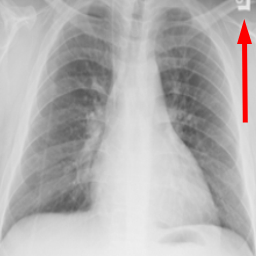

Many images in the dataset contain annotations or marks made during the image acquisition or afterwards by a radiologist. Examples of such images are presented in Fig. 3. Such symbols in the training dataset are known to generate biases as classifiers tend to target their attention to the presence of the symbols instead of genuine features of the image Rajaraman and Antani (2020); DeGrave et al. (2021). Therefore after the initial preprocessing, consisting of cropping and resizing all images containing such elements were removed.